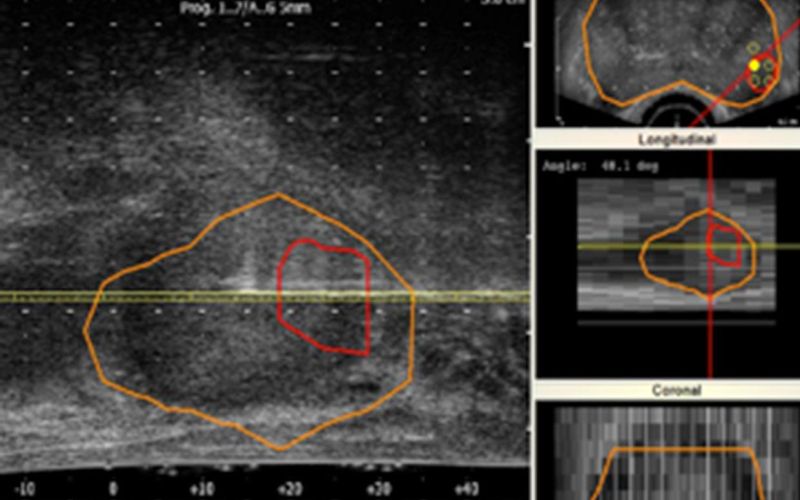

Biopsia por fusión: un mejor diagnóstico del cáncer de próstata

Te explicamos la técnica que combina la resonancia magnética y la ecografía para lograr una detección más precisa del tumor prostático

La biopsia por fusión es una de las técnicas innovadoras más eficaces para detectar el cáncer de próstata. La combinación de resonancia magnética y ecografía no solo facilita el momento de la exploración de la próstata, también consigue cen...

Avances en la detección del cáncer de próstata

La combinación de resonancia magnética y ecografía mejora la detección de tumores de riesgo

Uno de los cánceres más diagnosticados en hombres es el cáncer de próstata. Según cifras de la Sociedad Española de Oncología Médica, se detectan cerca de 30.000 casos al año. A estos alarmantes datos se suma el hecho de que, en ocasiones, ...

Biopsia de próstata mediante la fusión de Resonancia Magnética y Ecografía

El doctor Miguel Ángel López Costea, especialista en Urología del Hospital Quirónsalud Barcelona, nos explica cómo la combinación de la resonancia magnética y la ecografía permite localizar las lesiones para proceder a la biopsia y así determinar qué pacientes son susceptibles de ser operados y a cuáles administrar tratamientos locales